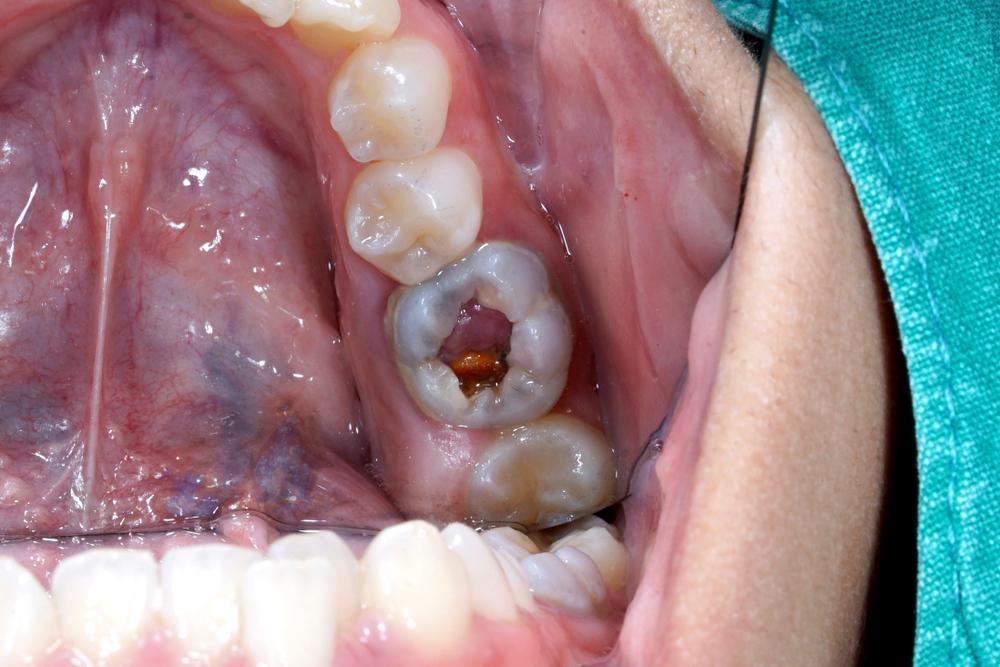

Polip pulpa atau pulpitis hiperplastik adalah pembengkakan jaringan pulpa pada gigi berlubang sebagai reaksi terhadap iritasi akibat pembusukan gigi.

Umumnya, pembusukan gigi membuat pulpa gigi mati. Pulpa merupakan jaringan ikat yang terdapat pada bagian tengah gigi, tepat di bawah lapisan dentin gigi.

Namun, kondisi ini menyebabkan hal sebaliknya karena iritasi malah membuat jaringan pulpa terus tumbuh.

Pulpitis hiperplastik merupakan bentuk pulpitis irreversibel. Ini berarti ketika Anda mengalaminya, jaringan pulpa tidak dapat pulih kembali meskipun penyebabnya dihilangkan.